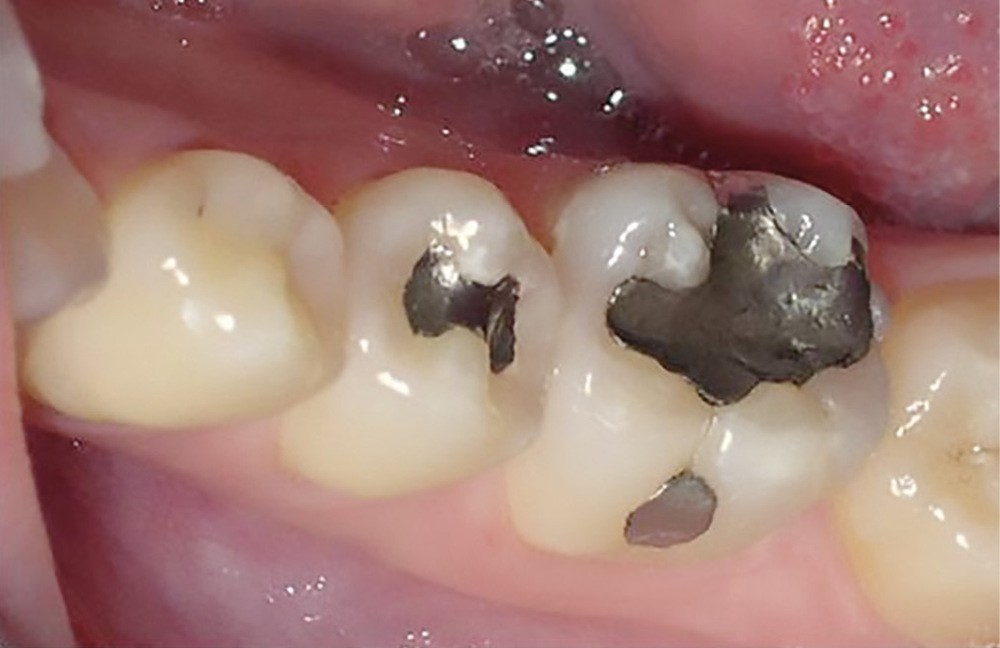

La consommation de produits acides a augmenté de manière exponentielle ces dernières années. On retrouve ceux-ci dans des aliments courants (boissons gazeuses, jus de fruit, en-cas sucré…) (fig. 1 et 2).

Nutritionnistes, médias et réseaux sociaux ont fait la part belle au régime à base de jus de citron à jeun, le matin : ce qui était présenté comme merveilleux pour le réveil intestinal et la perte de poids était en fait désastreux pour les organes dentaires, touchant de nombreuses adolescentes et jeunes femmes très sensibles à ce type de discours.

Le stress étant devenu omniprésent dans de nombreux secteurs d’activité, une frange de la population y est désormais assujettie, ce phénomène induisant ainsi de l’usure dentaire agissant en symbiose avec la prise de produits acides.